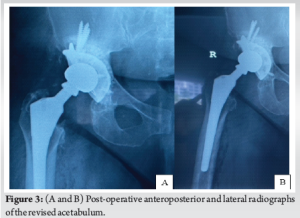

We incorporated the old incision and used a modified Hardinge approach to the hip. The soft tissues appeared healthy with minimal embedded metal debris, and there was no evidence of infection. The femoral head was easily removed, and the Morse taper was in good condition without signs of trunnionosis. After removing the acetabular shell, the exposed bony floor showed only minor cavitary defects, and the walls and columns were intact. We prepared the acetabulum in routine fashion, but without the benefit of morselized allograft, using a bone graft substitute (Medbone® Biomaterials, Portugal) to fill the defects. The bone graft substitute was contained by an acetabular cage (Contour, Smith and Nephew) secured with multiple screws. An all- polyethylene cup was cemented in place with Palacos® R (Heraeus Medical, Germany) cement, and a Bioball® adapter and femoral head (Merete, Germany) compatible with the Type one taper on the retained femoral stem, impacted in place (Fig. 2). The hip was reduced and cycled through its range of movement to ensure stability. The patient recovered well, and post-operative radiographs were satisfactory (Fig. 3). At the 2-year follow-up visit, the patient is delighted with her function, reporting only mild hip pain and has returned to full-time work, as shown in Table 1.